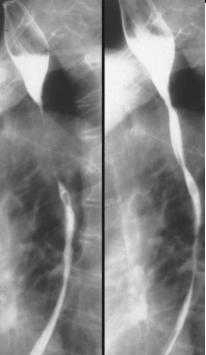

Oesophagite par reflux

: RGO c'est par la mal position cardio-tuberosite :

ouverture de angle de His avec cone d'attraction cardiale .

Signe de sensation brulure le longde l'oesophage ,

sensation acid peut aller jusqua bouche ( pyrosis ) associe

de symptome respiratoire et ORL sont des signe precedent de

oesophagite par reflux . Images radiologiques sont

restreinte au debut . TOGD ++ double de contrast se

donne des images des nodulations , des petites ulceres et de

atrophie epaisissement des plis muqueuses du portion

inferieure de oesophage . Parfois image de stenose

circonferentielle symetrique sur oesophage distal . Au cours

de oesophagite peptique image radiologique c'est image de

stenose circonferentielle symetrique en queue de rachis et

EBO

Image

radiologique de l'oesopagite de reflux sur TOGD de

double de contrast : Ouverture de angle de His

,petites ulceres et epaissisement de plie muqueuse

oesophagien etre en voyant. |

|

Stenose circonferentiele symetrique a distal de

oesophage . Technique radiologique TOGD +

technique de double de contrast baryte de oesophage

. . |

radiologique en double de contrast d'une stenose a

distal : oesophagite de reflux au grade 4

endobrachyoesophage(EBO) |